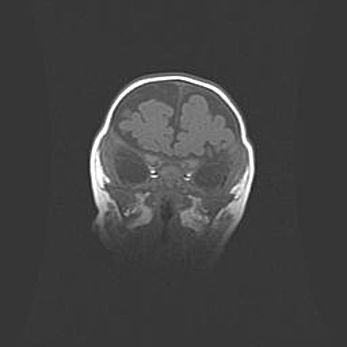

Церебральная ишемия II.

Возраст: 7 дней

Вес: 3350 г

Пол: женский

Окружность головы: 35 см

Срок гестации: 39 недель

Ишемия головного мозга – это состояние, которое развивается в ответ на кислородное голодание вследствие недостаточного мозгового кровообращения. У новорожденных она является следствием дефицита кислорода, что ведет к метаболическим расстройствам различной степени тяжести в тканях головного мозга, в том числе к развитию коагуляционных некрозов и гибели нейронов.